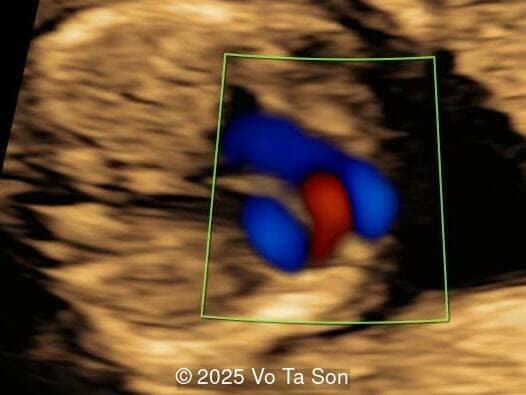

A woman underwent routine prenatal screening at 13 weeks. The non-invasive prenatal test (NIPT) showed low risk for common aneuploidies including trisomy 21, 18, and 13. However, first-trimester anomaly scan revealed multiple fetal anomalies.

Please describe the abnormalities and provide a syndromic diagnosis that best fits the presentation.